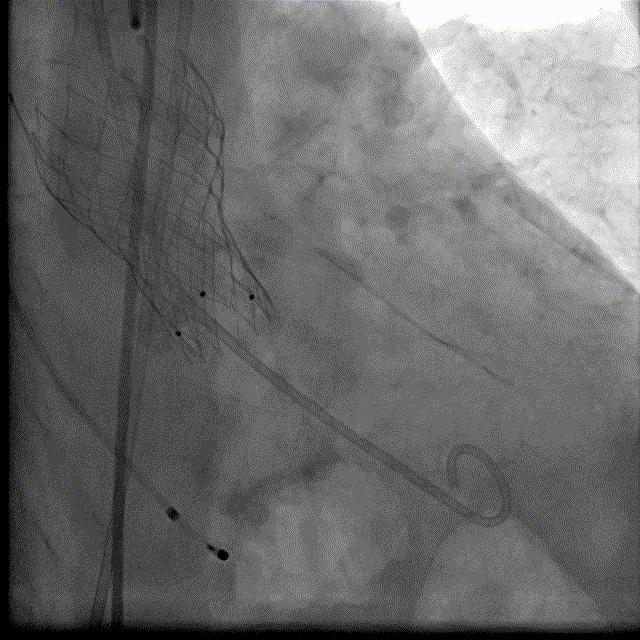

瓣膜释放DSA

瓣膜最终形态

术后III° AVB,持续,1周后安装起搏器

起搏器植入术后